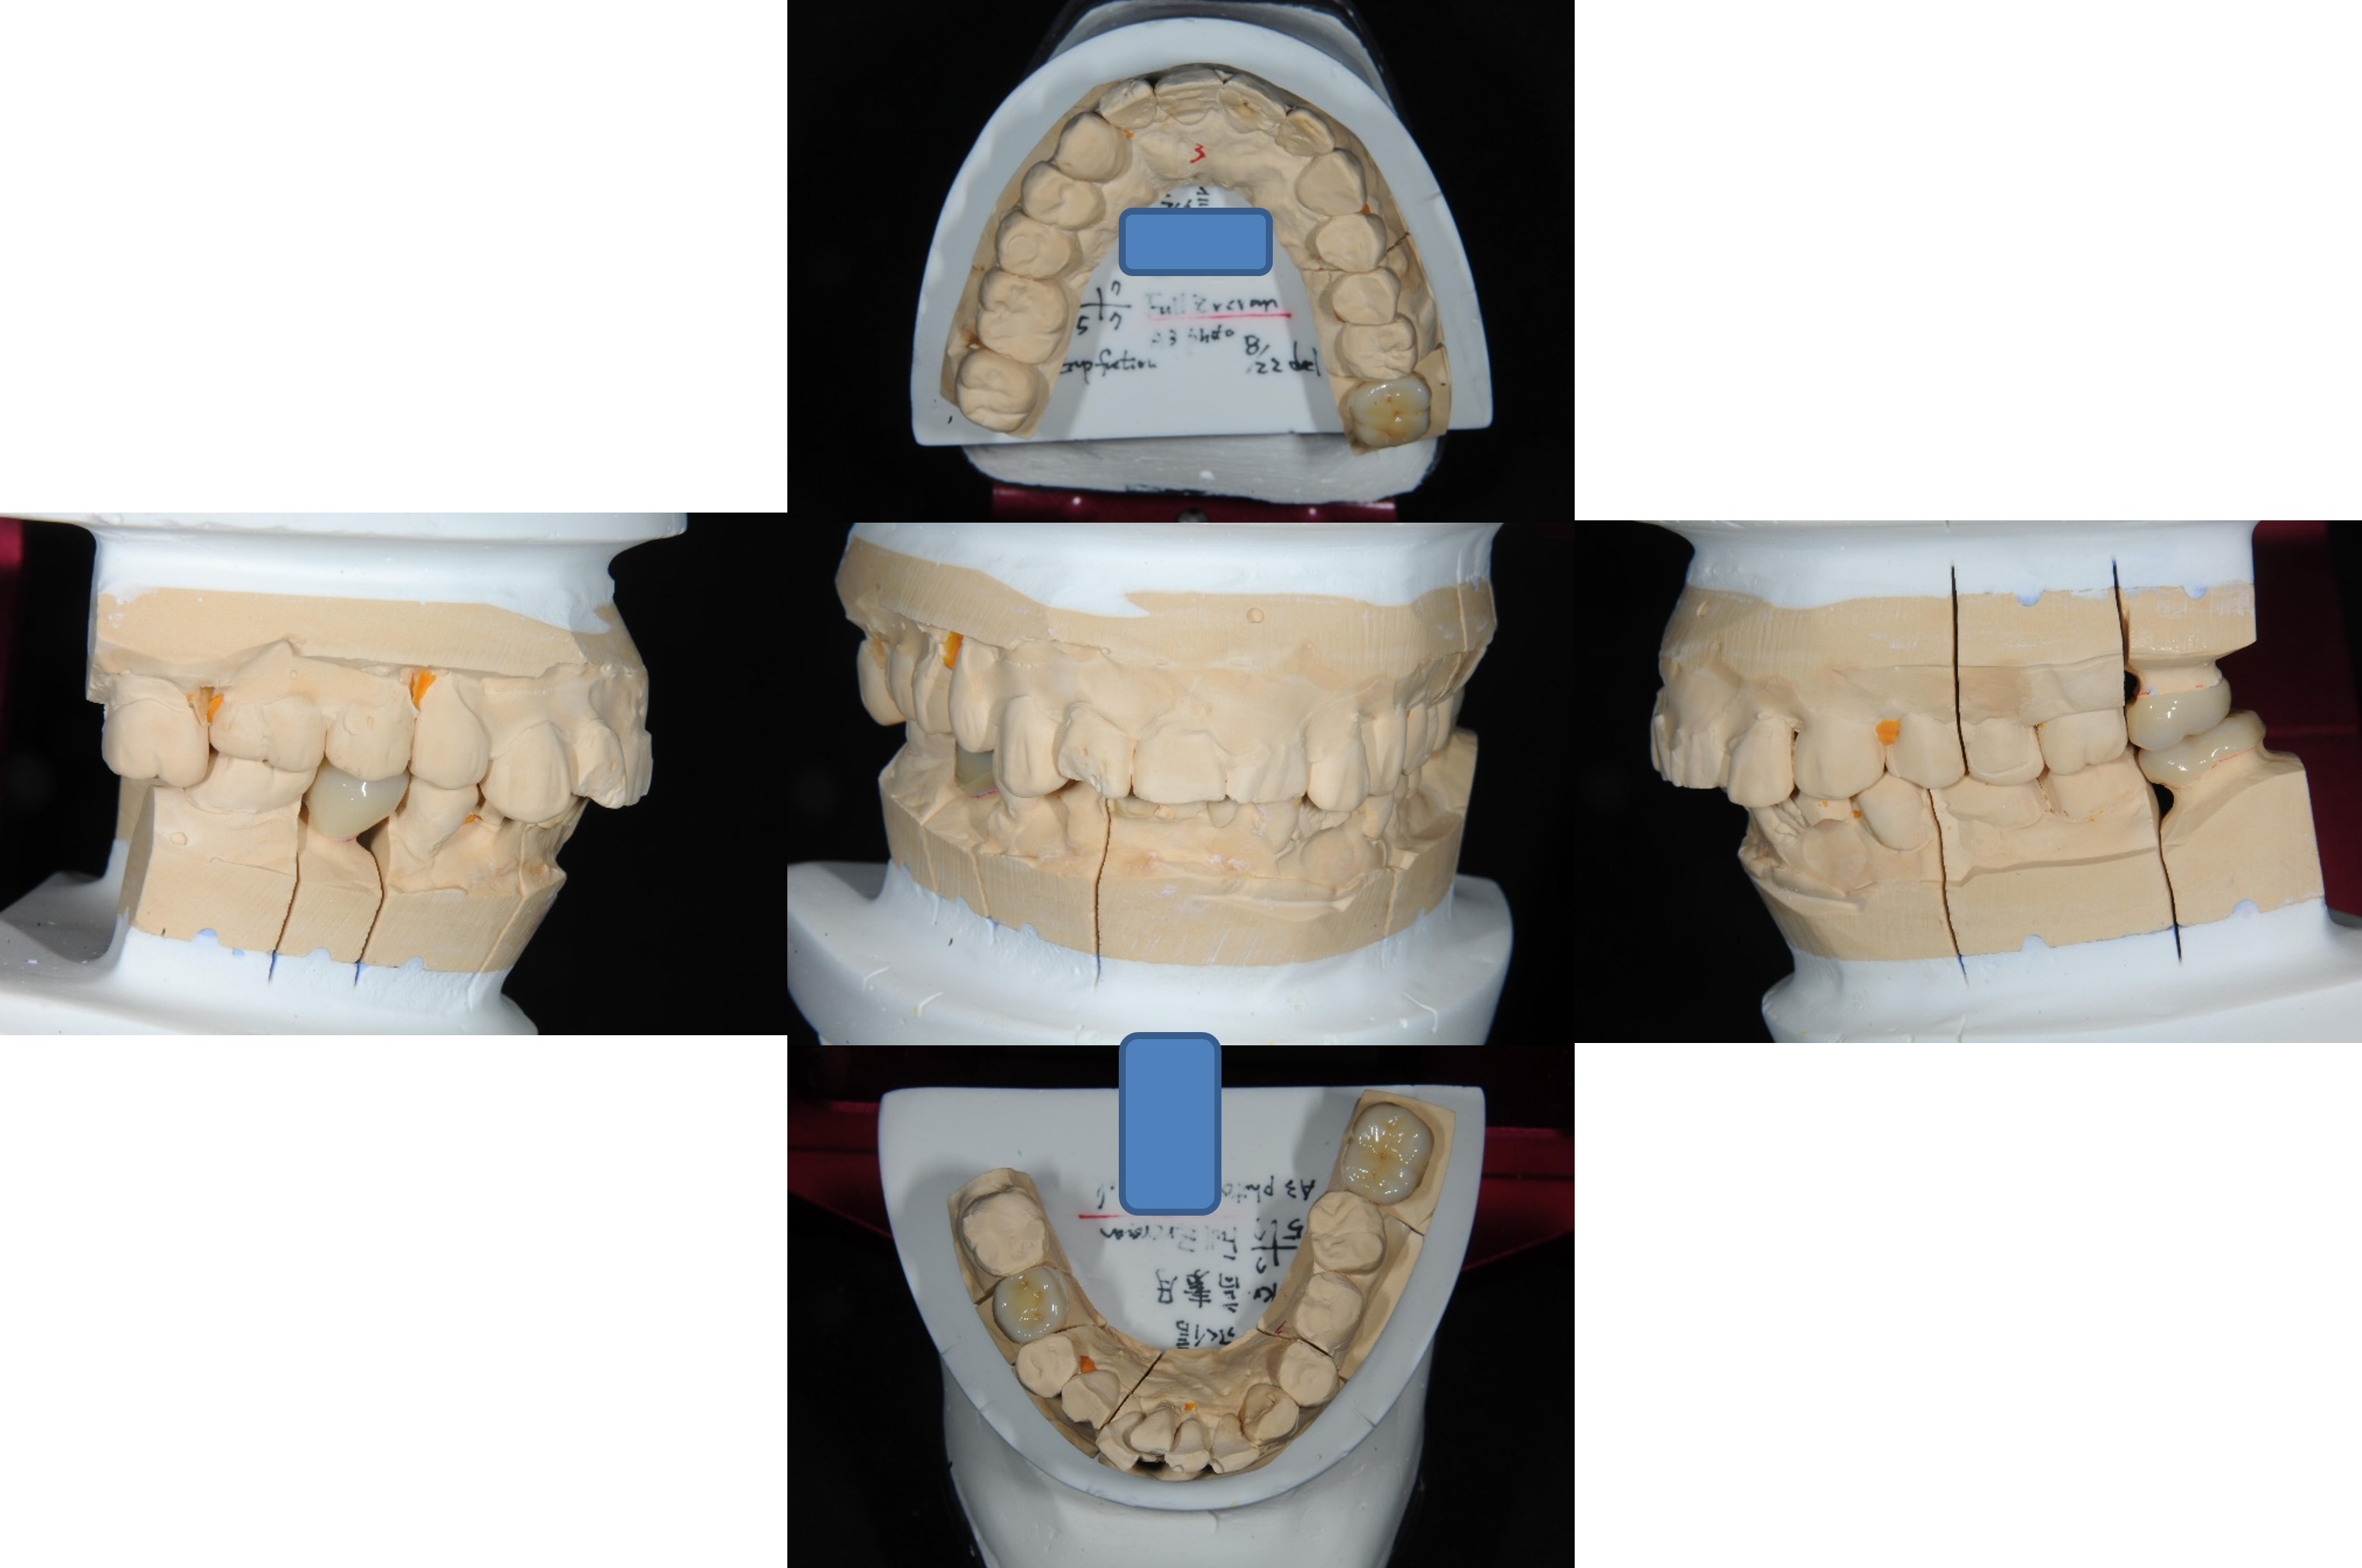

上面弓、上咬合器

技師於咬合器製作全瓷冠